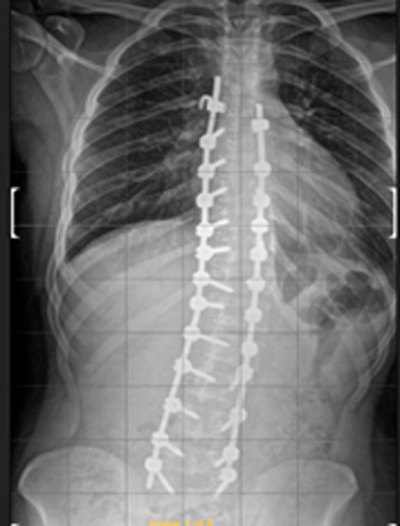

DIAGNOSI:

IPERCIFOSI DORSALE + SCOLIOSI DORSO LOMBARE

Radiografia della colonna in toto pre-operatoria

Intervento chirurgico eseguito:

STABILIZZAZIONE DORSO – LOMBARE CON OSTEOTOMIE CORRETTIVE

Radiografia della colonna in toto post-operatoria